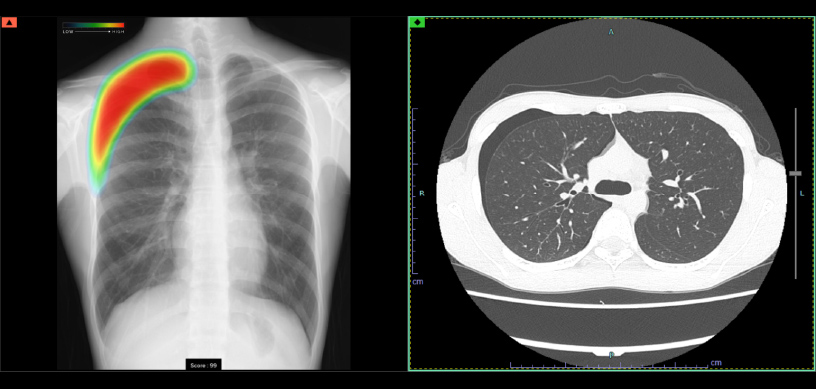

ヒートマップ表示機能

異常が疑われる領域をAIが自動的に解析し、確信度に合わせた表示を行います。確信度のスコアは0~100に分かれており、画像では色分けによるヒートマップとして表示されます。

スコア表示

0~100に分けられた確信度スコアの最大値が数値として表示されます。